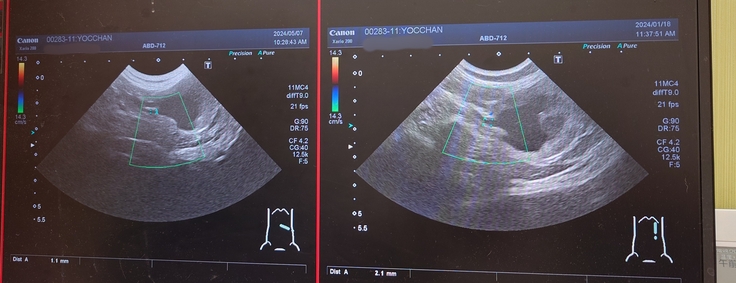

ヨッちゃんのエコー検査の結果です。

正常な右の腎臓腎盂。

画像の右側が前回のエコーで、左側が今回のエコー。

腎盂が肥大している左の腎臓。

左側の拡大していた尿管。

左側の腎盂は相変わらず肥大したままでエコーが黒く写っていました。

腎臓のサイズは右側の腎臓が45.8mmから42.1mm、左側の腎臓が39.4mmから35.7mmになっていて、前回よりも腎臓の大きさが縮小していて、もしかしたら腎臓の機能が低下しているのかもしれないということでした。ヨッちゃんの症状は良くなることはないという覚悟は頭の片隅に置いてるつもりですが、やっぱり聞くと毎回ガビーンとなります😨

でも、尿管拡張していて腎盂腎臓が肥大している左側の尿管が2.1mmから1.1mmに細くなっていてこれは良い結果だったので安心しました😊